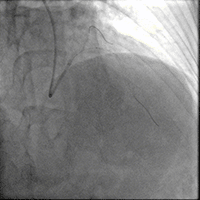

造影如下

患者左主干前三叉1,0,1型病变,主干末端偏心40%狭窄;前降支病变自开口延续至中段,口部80%狭窄,中段80%狭窄,病变位置钙化严重;回旋支近段约30%轻度狭窄,第一及第二钝缘支开口80%局限病变。